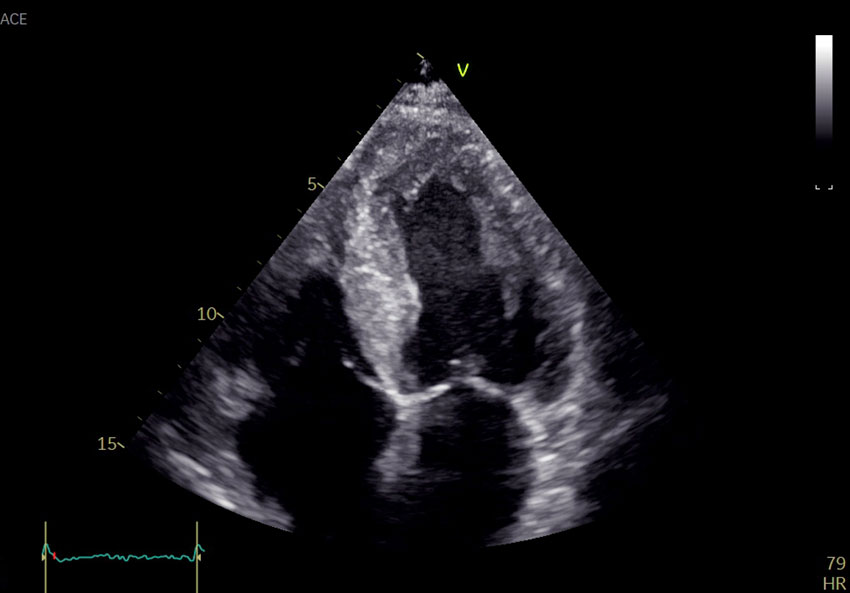

Ekkokardiografi avdekket global biventrikulær hypertrofi med endediastolisk septumtykkelse 17 mm (6–10 mm) (figur 1). Det var redusert langakseforkortning med relativt bevart funksjon apikalt. Myokard hadde et påfallende spettet ekkosignal, mest uttalt i septum. Ejeksjonsfraksjonen var 45 % (≥ 52) og den globale longitudinelle tøyningen −12 % (−18 til −22). Venstre atrium var dilatert. Det ble ikke avdekket klaffefeil av betydning. Pasienten hadde ingen synlig perikardvæske. Koronar angiografi ble utført påfølgende dag og avdekket ingen signifikante stenoser. Funn av økt veggtykkelse, spettet myokard og påfallende redusert langaksebevegelighet med bevart funksjon apikalt vekket mistanke om avleiringssykdom, og videre utredning ble igangsatt.

Histologisk undersøkelse av endomyokardbiopsiene viste at vevet bandt kongorødt, forenlig med amyloidavleiring. Immunfarging av endomyokardbiopsiene viste forekomst av både transtyretin og kappa-lettkjede (figur 3). Laserdisseksjon med massespektrometri viste at både transtyretin og kappa-lettkjeder var blant de dominerende proteinene, med overvekt av transtyretin, forenlig med både kardial transtyretin og amyloid lettkjedet kardiomyopati. Monoklonale plasmaceller (kappa+) utgjorde 10–12 % av cellene i benmargsbiopsien. Det var amyloidavleiring også i benmargen. Som ledd i utredningen ble det utført fettvevsbiopsi uten funn av amyloid. Nyrebiopsi ble ikke gjentatt. Computertomografisk røntgenundersøkelse viste ingen lytiske lesjoner i skjelettet.